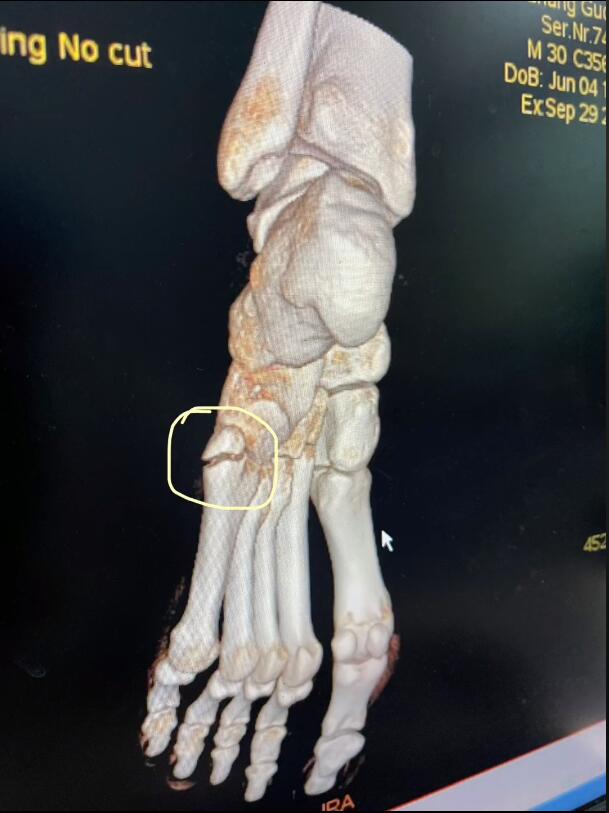

张国伟还晒出了自己检查的报告单,第一张是DRI,左足第五跖骨底部骨折。

他第二次拍CT的结果是左足第五跖骨基底部骨折,左侧第五趾关节边缘多发小钙化灶。

张国伟在晒出自己将接受手术治疗后还能调侃一般的发视频,应该是没有大碍。不过8月20日复出9月29日就遭遇伤病属实有点倒霉啊。根据张国伟的叙述他是因为训练太猛,过度疲劳导致的骨折。